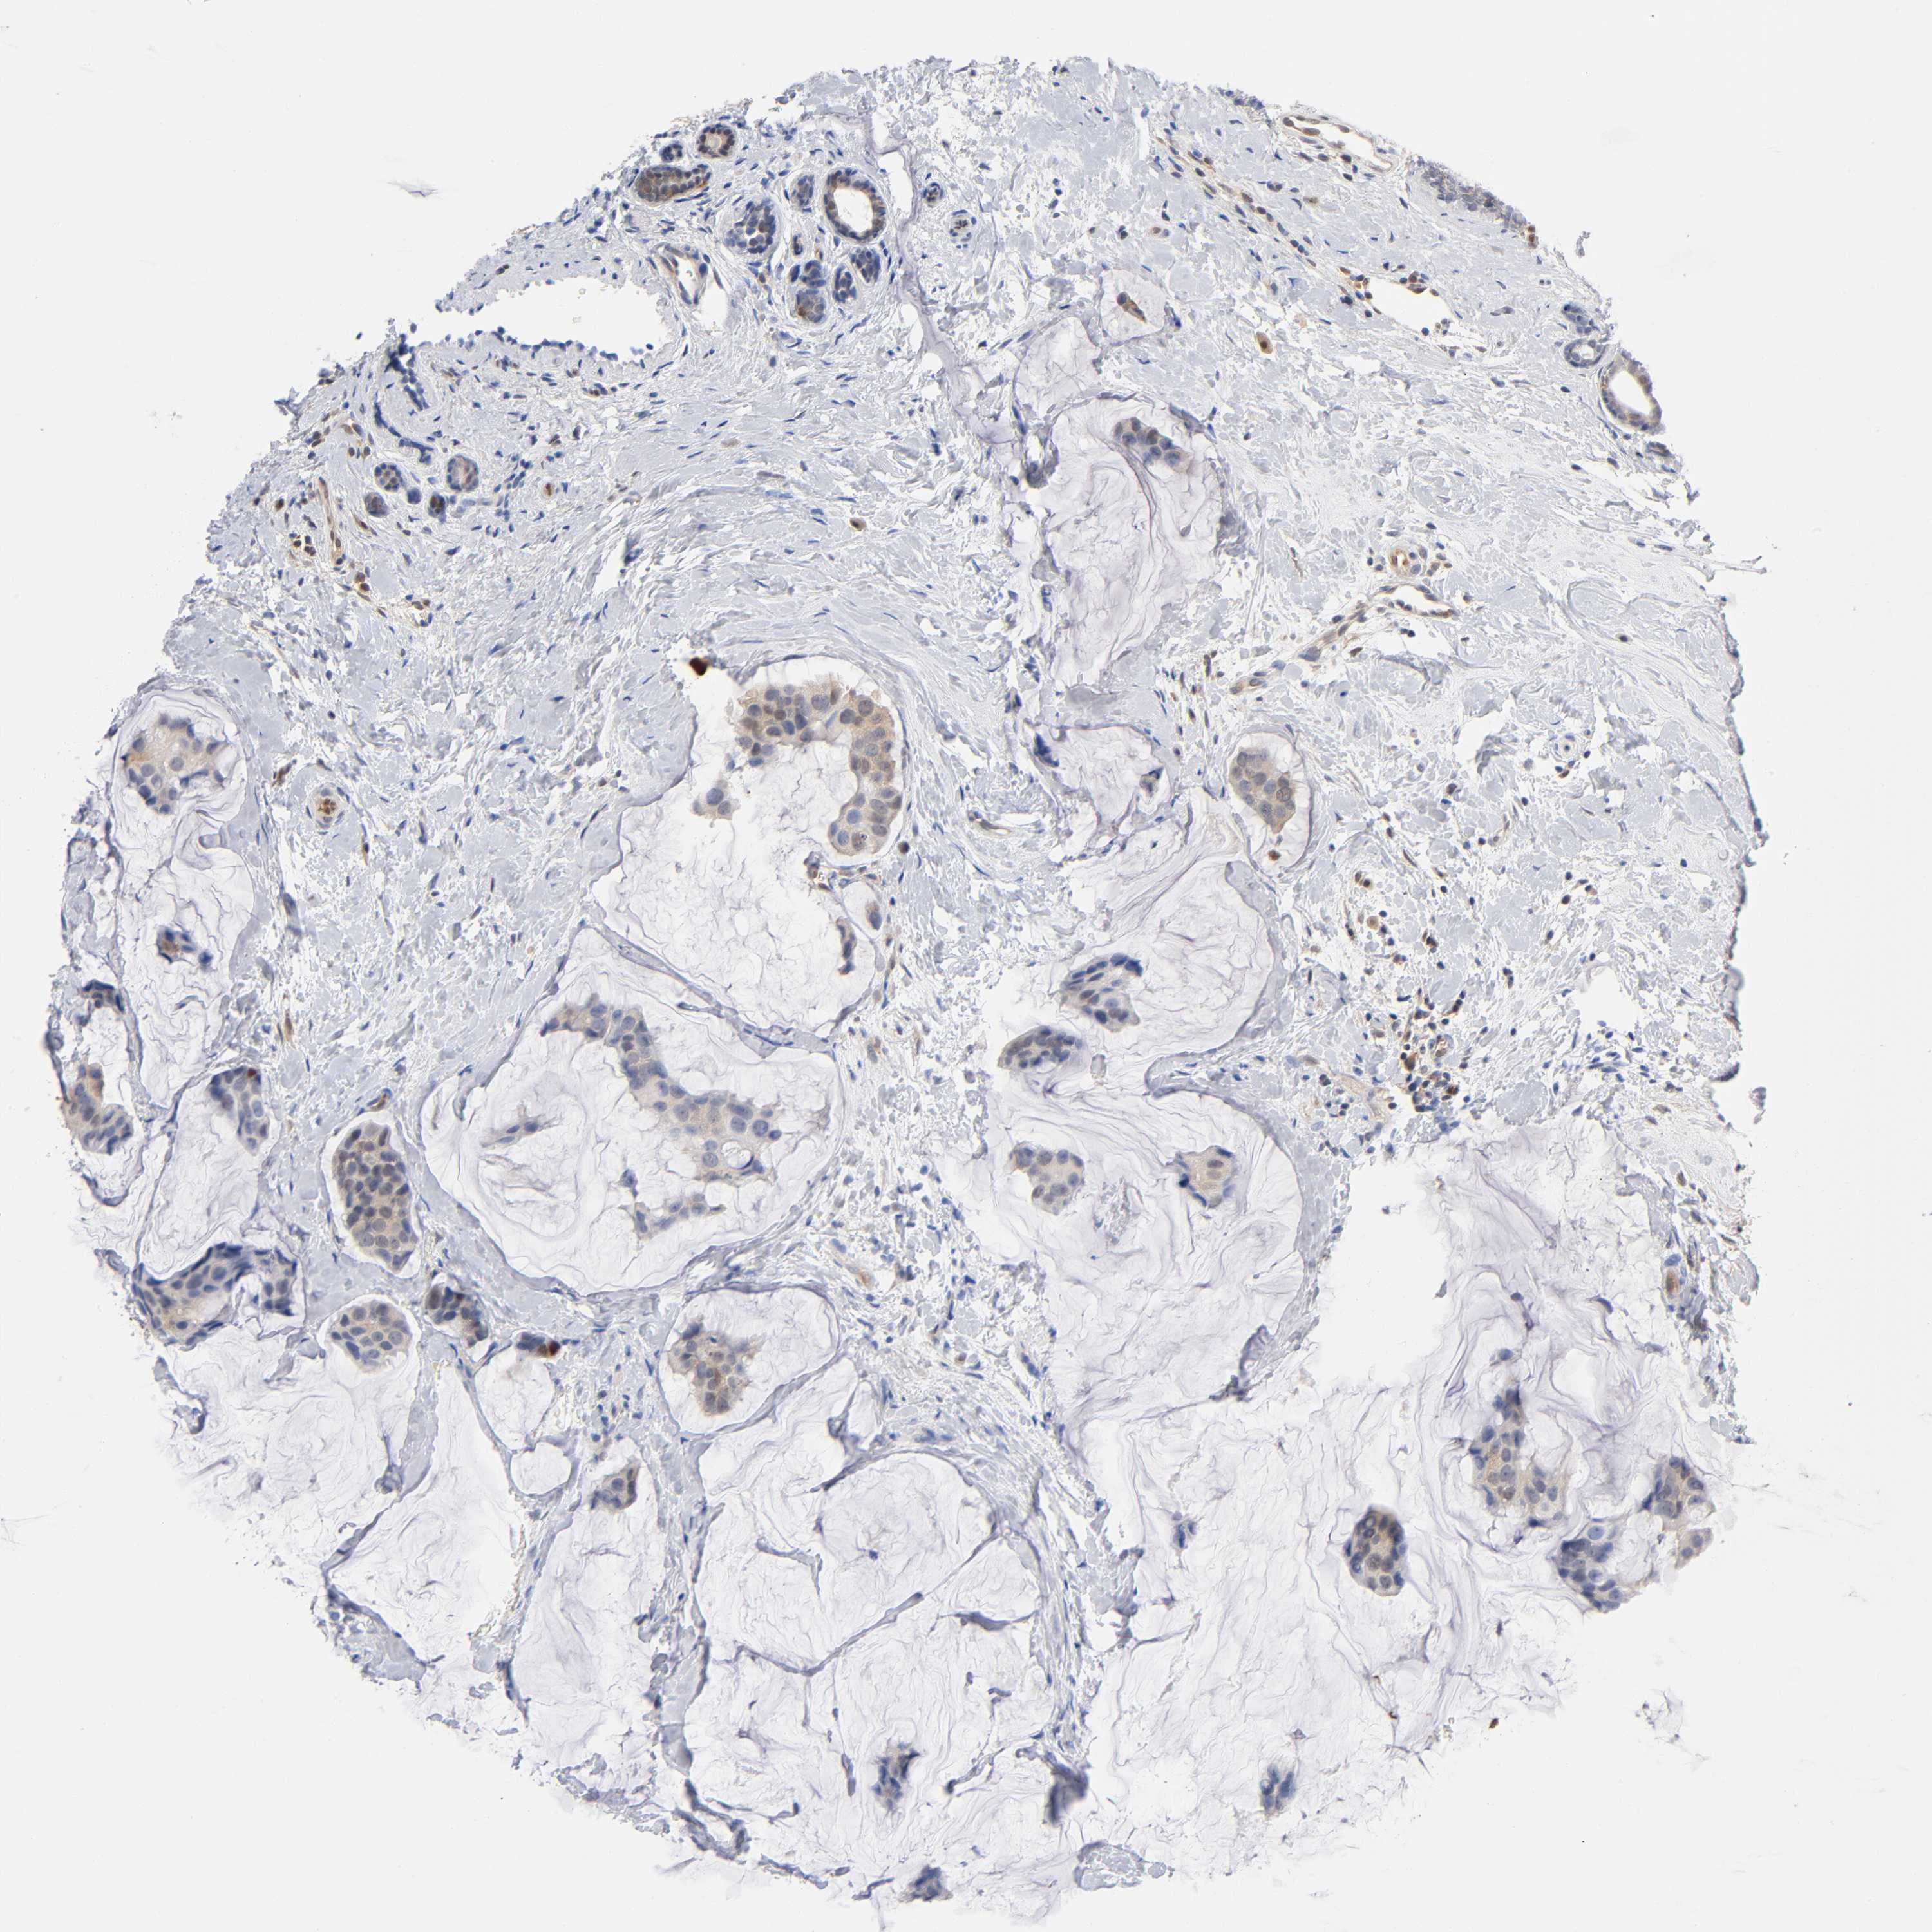

BRCA TCGA BRCA VALIDATION PROTEIN EXPRESSION